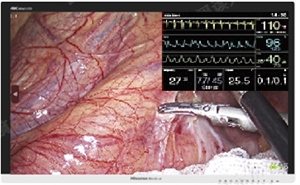

在外科手术中,医生经常要查看患者心电图、MRI、CT、超声等影像信息,方便对比不同图像,综合评估患者的情况,为手术方案提供参考。基于这一临床使用需求,海信4K 3D内窥显示器在3D模式下,使用PiP功能屏幕同时显示2D监测生命体征图像,将所有病人相关影像集中到一张屏上显示,减少医生手术风险,提高医生工作效率。